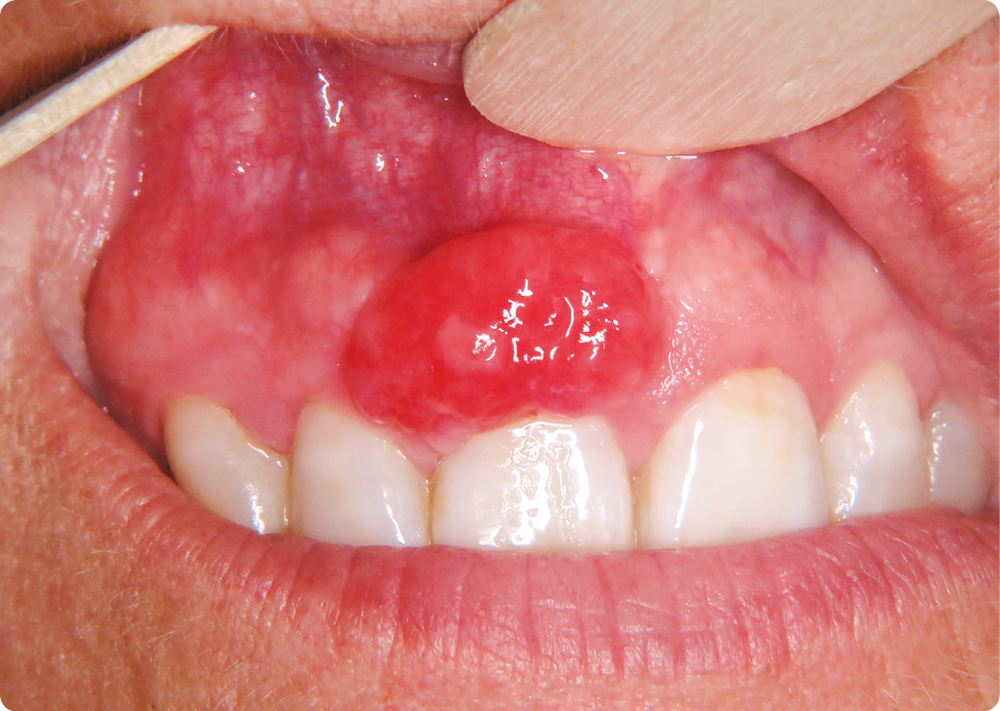

• À l’inspection, on observait un nodule érythémateux d’environ 1 cm de diamètre, de surface lisse, d’aspect pédiculé, développé aux dépens de la papille gingivale située entre 11 et 12. La palpation du nodule de consistance ferme provoquait un saignement.